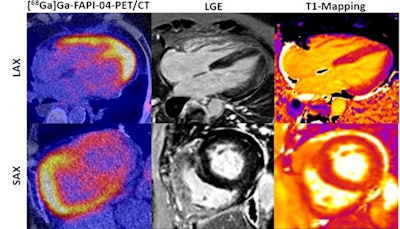

In a proof-of-concept study, researchers at University of Erlangen-Nuremberg tested whether gallium-68 (Ga-68) FAPI-04 tracer uptake could differentiate scleroderma patients with myocardial fibrosis from those without myocardial fibrosis. They observed consistent Ga-68 FAPI-04 uptake and suggested the approach could improve early assessment of treatment responses.

Results showed that Ga-68 FAPI-04 tracer uptake was increased in scleroderma patients with MF, with higher uptake in patients with arrhythmias, elevated serum markers for myocardial dysfunction, and MRI-positive regions. Myocardial biopsies from Ga-68 FAPI-04-positive regions confirmed the accumulation of fibroblasts expressing FAP, they found.